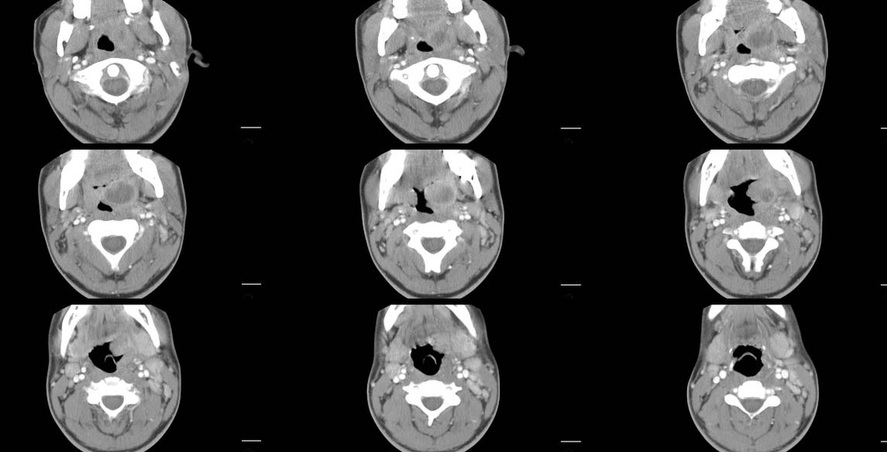

There is a focal oval left parapharyngeal lesion which produces marked pharyngeal narrowing by compressing but not invading/eroding into the airway. The lesion demonstrates low attenuation centrally with peripheral enhancement.